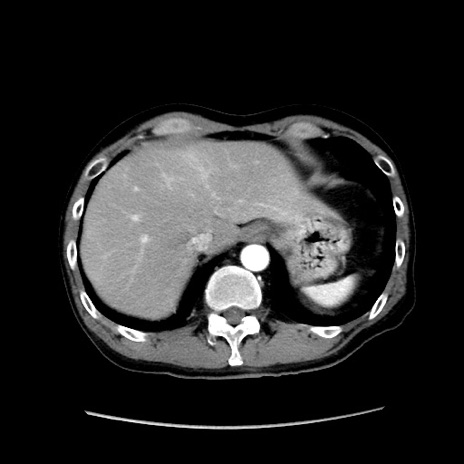

症例37(横断像)

【症例】40歳代 男性

【主訴】腹痛

【現病歴】4時間ほど前に電車に乗車中に臍部上より腹痛出現。徐々に増悪し起立困難となり、救急外来受診。生ものは数日食べていない。今朝お雑煮を食べた。

【身体所見】BT 36.8℃、BP 117/84mmHg、HR 91/min、SpO2 97%、苦悶様、腹部:臍上部広範囲圧痛あり、反跳痛±

【データ】WBC 8100、CRP 0.03